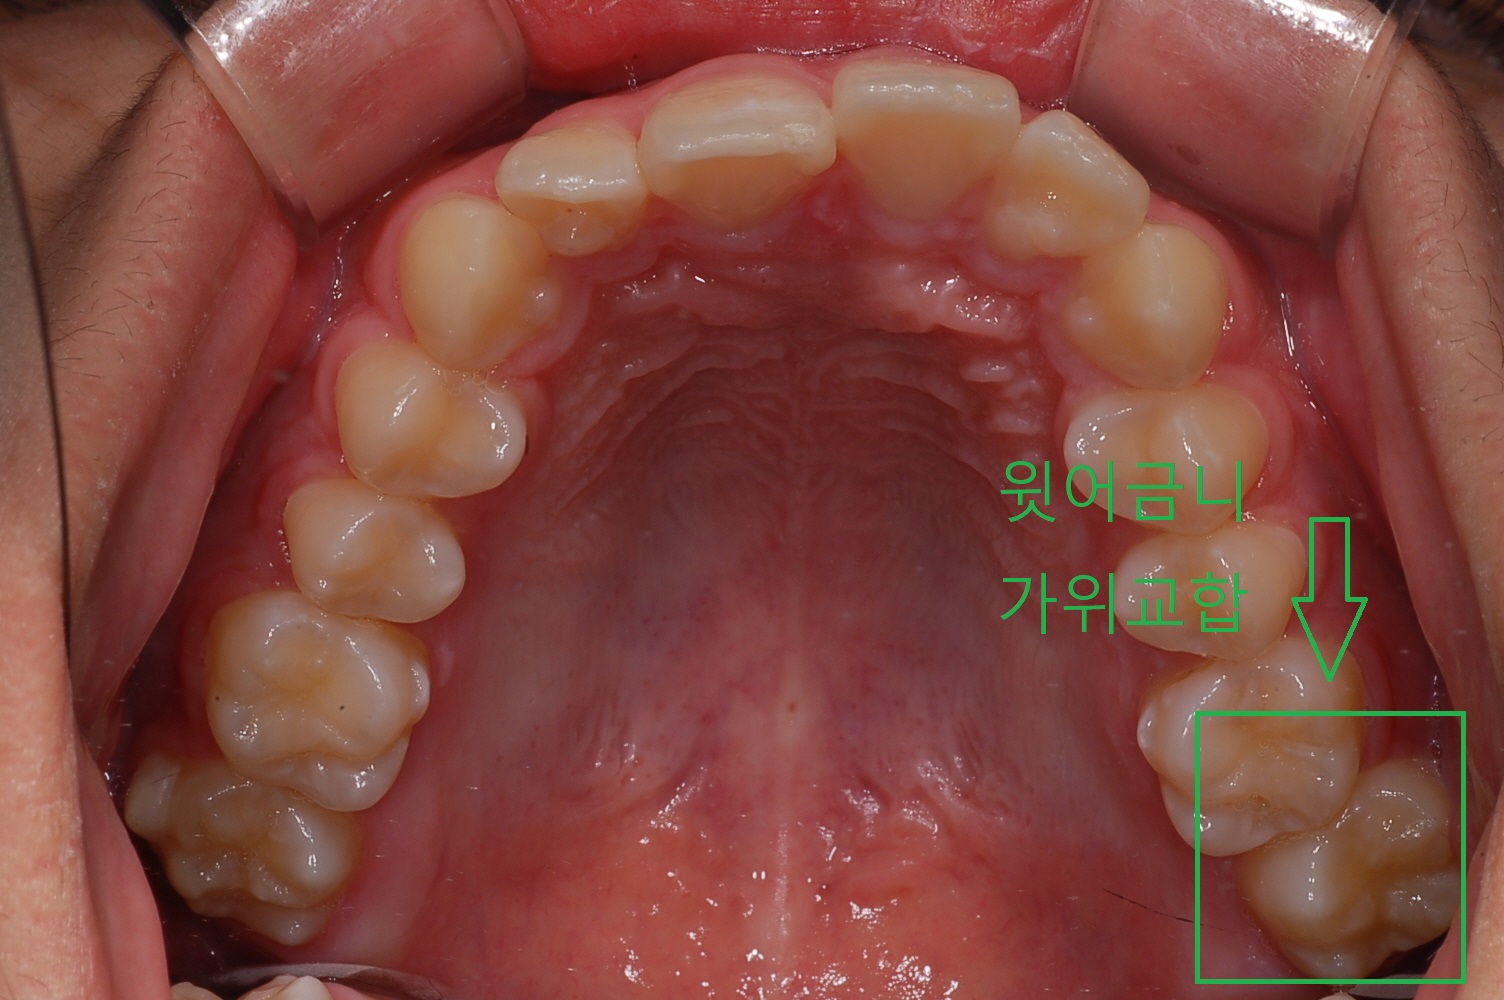

아들치아 교정하면서 공부도 참 많이 하게 되네요. 영구치의 치아상태가 위, 아래 어금니가 누운 상태로 지냈습니다. 이것을 가위교합이라고 합니다.

집에서 쓰는 가위 아시죠? 이처럼 위,아래 어금니가 맞지 않은 상태를 가위교합이라고 합니다.

위,아래 어금니가 안.밖으로 쓰러져 있는 상태입니다. 이 상태로 계속 두면 부정교합 시간이 길어져 치아가 더욱 틀어짐이 심해지며 결국은 발치를 빨리 해야 될 상황이 오게 됩니다.

◎ 아들치아교정 전 상태확인 (가위교합사진)

- 「윗 어금니 가위교합 1개」

- 「아래 어금니 가위교합 1개」